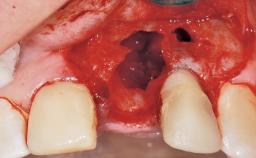

A 77-year-old male patient was referred for the management of frequent and repeated acrylic fracture of his existing mandibular fixed full-arch implant-supported metal/acrylic prosthesis. He also complained about softtissue soreness and the lack of retention and stability of his maxillary removable partial metal/acrylic prosthesis. Both prostheses had been delivered two years previously as part of his full-mouth rehabilitation (caries, tooth wear, tooth fracture). His medical history revealed high blood pressure, controlled with the use of antihypertensive medication.